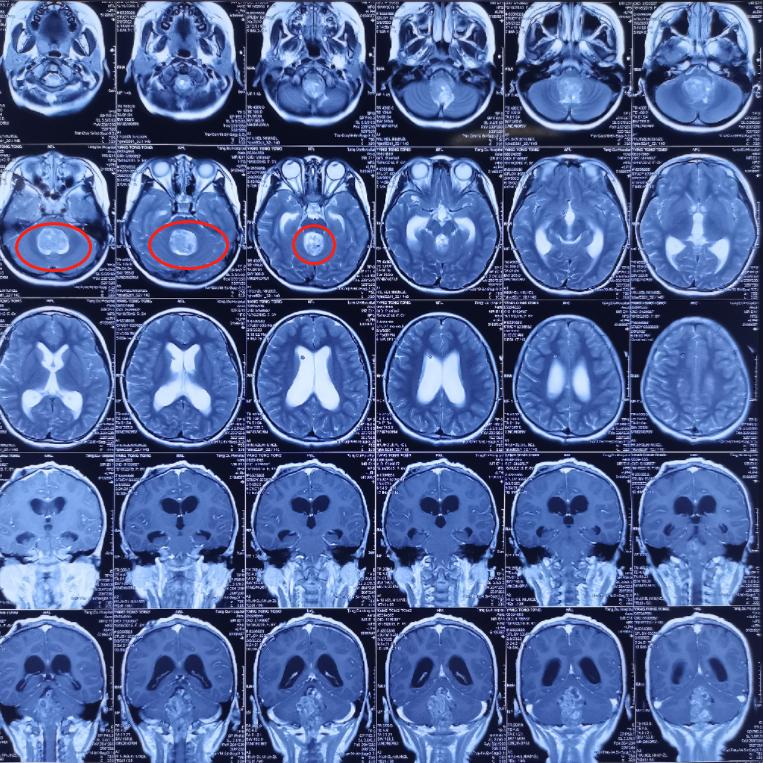

术前影像学资料: